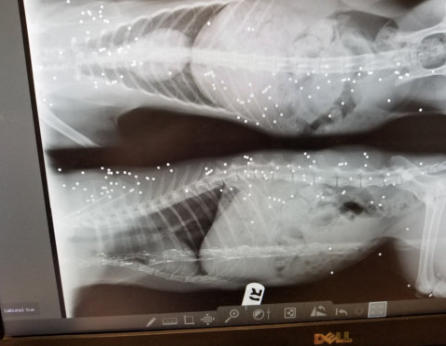

His x-rays show the life of hell he had endured

Blind Gender: Male Approximate age: Arrived From: North Carolina Arrival Day: August 2018 Uncle Fester spent his life trying to stay out of the way of people who might do him harm, cars, and other dangers of life for a blind cat. This was his story, until he came to BCR in 2018. By the time a good Samaritan had alerted someone about this poor cat who had been looking for food, he’d been through so much. When he got to BCR, he had many wounds and a broken leg that had healed incorrectly. It’s most likely that Uncle Fester lost his sight due to an untreated upper respiratory infection. When we took Fester to the vet for his first thorough medical exam, his X-ray revealed that he had been shot at close range with bird-shot. Those pellets are still visible under his skin. Although they aren’t painful, they are there as a reminder of his past. However, Uncle Fester’s story has a very happy ending! This kind and gentle cat today lives a safe, healthy life full of love and attention. Despite his horrible life on the street and the abuse he suffered, he is now in a place where he will never be abused, afraid or hungry again. He is – in spite of all he’s endured - a very loving cat who still loves and trusts people. Uncle Fester is also a great friend to his fellow BCR cats, always trying to make new arrivals to his room feel safe. All of them like to cuddle with him! You may catch Uncle Fester in a cuddle puddle on our live 24-hour cameras in House 2, Room 2. Live Pet Camera HERE

The horrible things humans think is ok to do to an innocent animal. That is bird shot, I would guess from a very close range. We were horrified when we saw the x-ray!